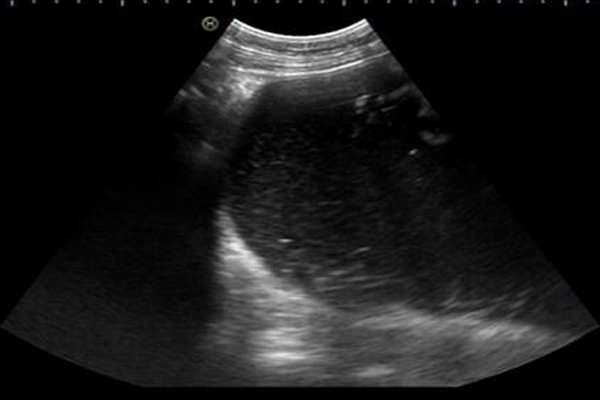

患者,19岁,因“阴道流血20天,发现腹部包块1天”在外院检查,超声提示腹腔至盆腔内囊实性肿物。患者及家属得知病情后,找到附属三院妇一科关郁主任。关郁主任详细了解了病情,结合辅助检查,初步诊断为盆腹腔巨大包块,卵巢畸胎瘤可能性大,其治疗方式为手术治疗。因患者年轻要求美观,故行微创手术。手术当日,予以先行超声定位,麻醉成功后,于定位点处穿刺,抽出暗褐色液体约2000毫升,肿物明显缩小,上缘下降至脐下,这样就可以将直径约30厘米盆腹腔包块缩小成下腹部包块。腹腔镜探查见右侧卵巢肿物直径约15厘米,吸引器入囊腔内吸出大部分液体,为防止囊内液流入盆腹腔,术中关郁主任提出将囊皮自左侧穿刺孔牵出,自穿刺孔处取出囊内组织物。逐渐切除卵巢多余囊皮切除并清理干净后,将卵巢成形缝合,恢复卵巢正常形态,并还纳至盆腔内。巨大肿物经腹腔镜顺利切除,患者术后恢复良好。

腹腔至盆腔内囊实性肿物